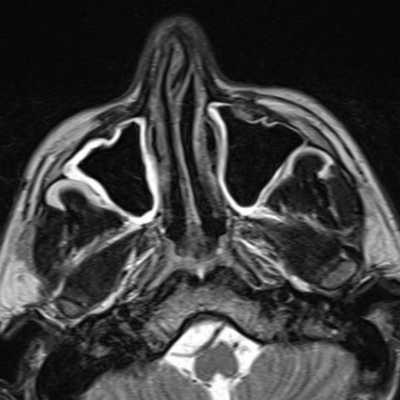

3. МРТ при глиоме носа:

• Т1ВИ:

о Объемное образование преимущественно смешанной или низкой сигнальной интенсивности

о Редко визуализируются извилины коры (серое вещество)

• Т2ВИ:

о Гиперинтенсивный сигнал, обусловленный глиозом

о Ликвор вокруг образования, сообщающийся с субарахноидальном пространством, отсутствует

• Т1ВИ С+:

о Диспластическая ткань обычно не накапливает контраст:

- Периферическое контрастирование интраназального образования может быть обусловлено слизистой оболочкой носа

(Слева) При аксиальной МРТ Т1 С+ определяется контрастное усиление в центре большой экстраназальной глиомы, слегка смещенной от средней линии. Накопление контраста в экстраназальной глиоме нетипично.

(Справа) При аксиальной МРТ Т1 С+ визуализируется хорошо отграниченная срединная экстраназальная глиома спинки носа с диффузным контрастным усилением. Настолько выраженное накопление контраста - редкий признак глиомы носа.